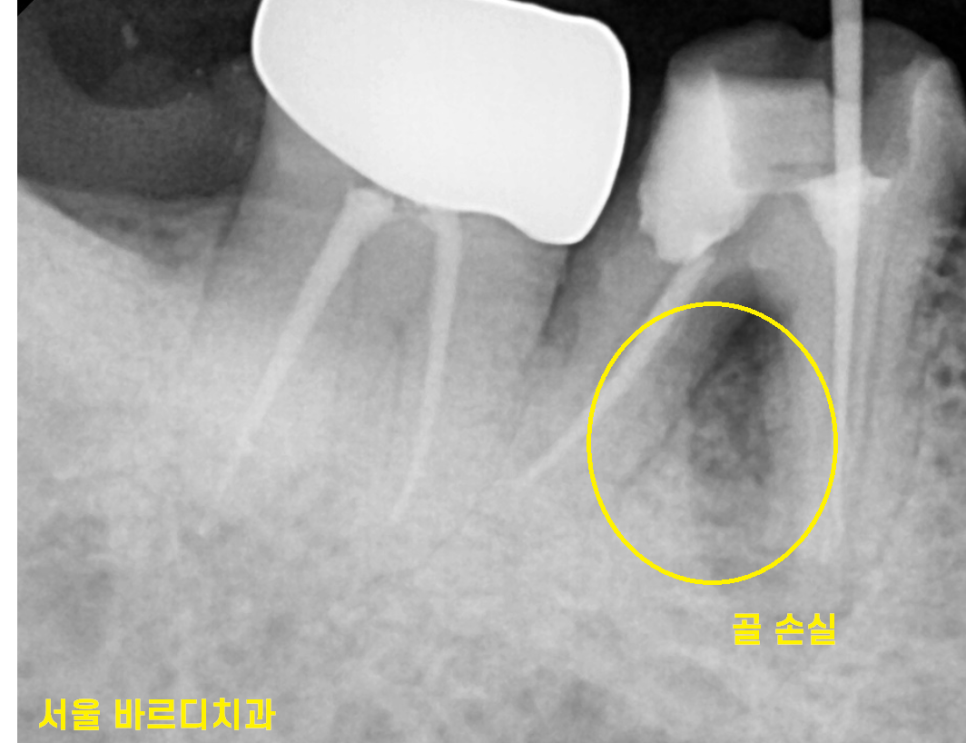

치아 뿌리에 염증이 아주 심하거나

심한 충치로 치아 내부까지 손상이 되어있거나

mta를 사용하면 치아를 뽑지 않고

최대한 보존이가능한데요.